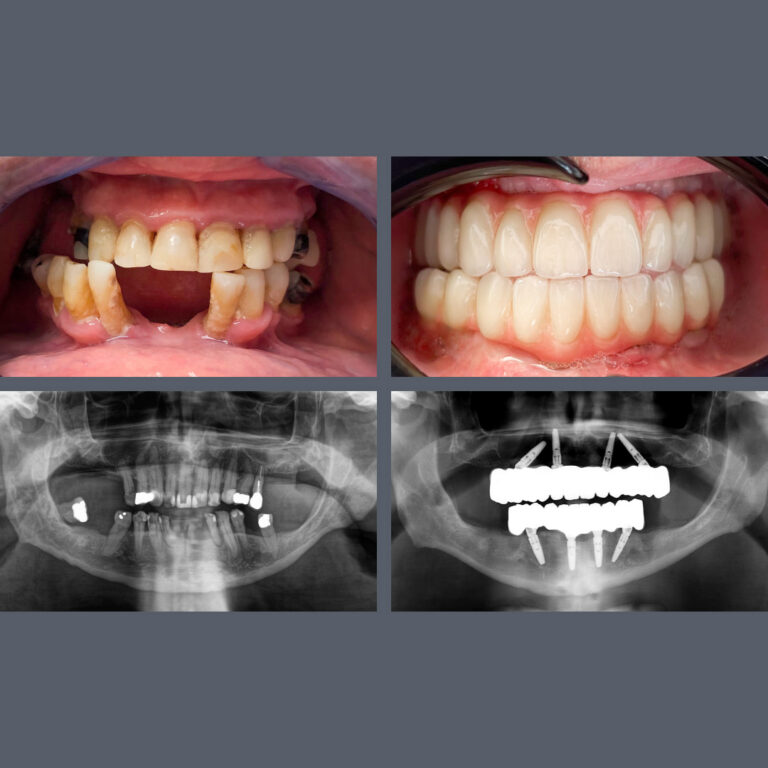

Tandimplantatproducenten Nobel Biocare har tildelt Madenta prisen “All-on-4® Center of Excellence”. Prisen gives til klinikken for det højeste antal All-on-4® behandlinger i Budapest og for enestående faglighed på højeste niveau.

Med denne anerkendelse regnes vores tandlæger blandt de førende specialister i Ungarn inden for All-on-4® behandlinger. Vi går ikke på kompromis og anvender udelukkende højkvalitets Nobel-implantater i vores All-on-4® behandlinger.

Specialiseret behandling giver smukke smil

Mange af vores udenlandske patienter kommer til os for implantater, kirurgiske indgreb og protetiske behandlinger, med håb om at kunne rejse hjem efter få dage med et både funktionelt og æstetisk smukt smil. Du er kommet til det rette sted! Vores specialister er internationalt anerkendte, og når de arbejder sammen på tværs af specialer, er næsten intet umuligt.